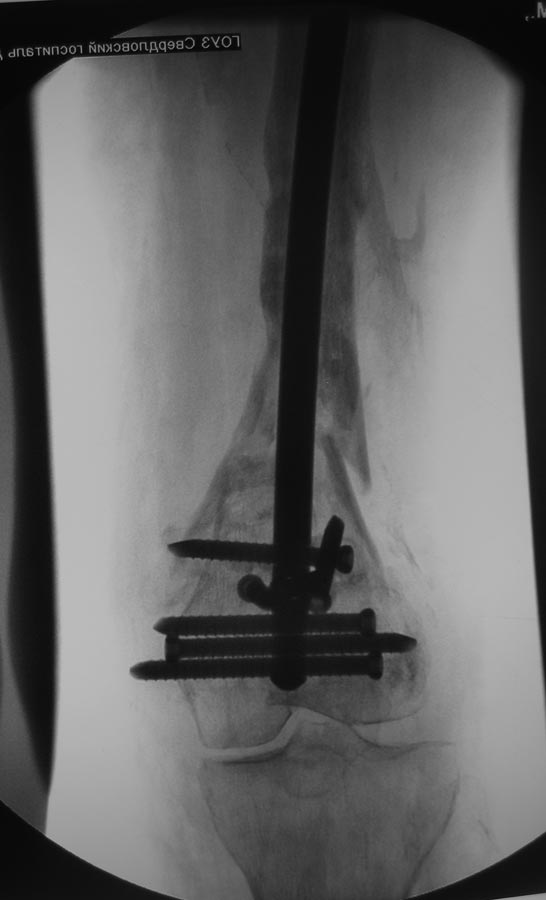

Уважаемые коллеги!Пациентка 72 лет, сочетанная травма в июле 2011. Одно из повреждений (кроме ЧМТ, грудной клетки, длительной реанимации) перелом дистального бедра. После временной фиксации в аппарате через 3 недели накостный остеосинтез. Раннее нагноение, попытки консеравативного лечения. Под наше наблюдение попала через 6 месяцев, гнойный свищ по наружной поверхности бедра, до пластины, нестабильная фиксация,миграция винтов, боли, постельный режим. Первым этапом удалена пластина, некрэктомия, бусы из цемента с а\б, апааратная фиксация. Заживление первичное. Вторым этапом снятие аппарта через месяц, замена бус, интрамедуллярный остосинтез, в последующем (через 1,5 месяца) бусы удалены, введены дополнительные винты из-за начинающейся миграции. Заживление первичное. В настоящее время 7 месяцев после последнего вмешательства, гвоздь динамизирован. На фоне улучшения общего состояния (пациенка активизирована, ходи с доп.опорой, болевой синдром незначительный) сохраняются эпизоды гипертермии проходящие на фоне а\б широкого спектра (авелокс). Р-граммы в динамике - отсутствие признаков нестабильности, резорбции, динамизация не исчерпана.Основная проблема - гипертермия, возобновляющаяся через 2-3 недели после прекращения а\б. Варианты:1) Наблюдать до 12-18 месяцев надесясь на консолидацию с последующим удалением 2) некрэктомия? 3) Резекция в пределах здоровых тканей с онкологическим протезом? Другие варианты

У меня пока складывается впечатление, что надо бы удалить гвоздь, поправить ось и пересинтезировать гвоздем с покрытием. Сейчас есть вальгус, гвоздь очень спереди, в дистальном отломке держится плоховато. То есть улучшить соотношение отломков и увеличить стабильность. Плюс рассверлить.

Про переднее положение гвоздя- это есть, но он точно в дистальном отломке, Сместить кзади не получилось из-за множественных дефектов от пластины, пороза, отклоняющие спицы просто режутся

За семь месяцев нет ни дополнительной резорбции, ни миграции винтов - какие причины сомневаться в стабильности? Новые отверстия для винтов при многих предыдущих -что добавит стабильность?

Канал был рассверлен, гвоздь 11,5 с покрытием из цемента